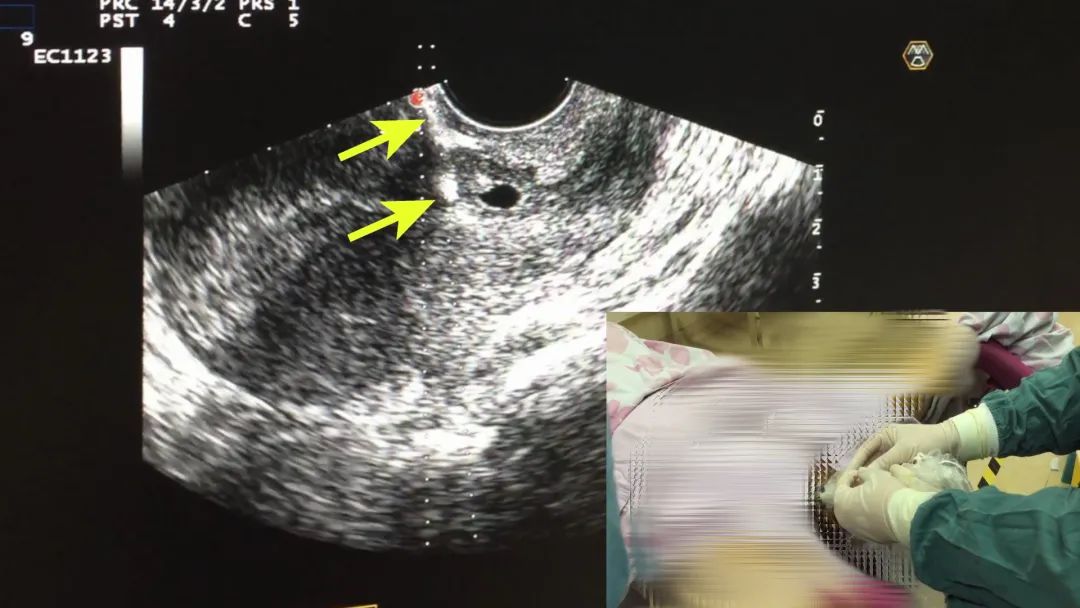

手术由超声科主治医生王小剑打头阵,她采用超声造影技术精确定位妊娠滋养层,并通过穿刺针将硬化剂准确注入滋养层周围的子宫肌层内,封堵丰富血供。

注射硬化剂

虽然穿刺部位的子宫肌层厚度为毫米级,但王小剑凭借娴熟技术,在15分钟内就顺利完成了整个操作过程。